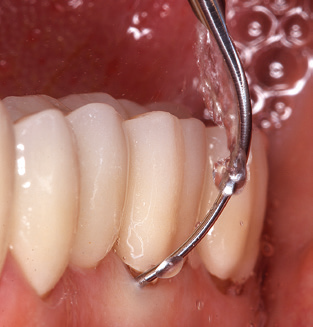

Das aktuelle Arbeitskonzept für die UPT

Als zentraler Bestandteil der UPT ist natürlich die Instrumentierung zum mechanischen Entfernen des Biofilms von vorrangiger Bedeutung. Der Ablaufplan einer UPT sieht zu diesem Zweck eine supra­, ggf. auch eine subgingivale Reinigung vor. Hier hat sich im Rahmen unseres Konzepts eine Kombination von Handinstrumenten und maschineller Reinigung bewährt. Für die maschinelle Vorgehensweise gibt es mehrere Optionen: Schallgeräte, Ultraschallgeräte sowie Pulverstrahlgeräte.

Die gute Ausleuchtung des Arbeitsfeldes stellt eine wesentliche Erleichterung dar. Bei dem von den Autoren genutzten System ist dies gelungen, indem ein 5­facher LED­Ring in das Handstück integriert wurde. Natürlich werden für dieses System unterschiedliche Arbeitsspitzen für die jeweiligen Indikationsbereiche angeboten. Eine gerade, universell einsetzbare Spitze ist das Basisinstrument zur maschinellen Instrumentierung natürlicher Zähne (Abb. 5a und b). Für schwer zugängliche Bereiche im Seitenzahnbereich werden gebogene Spitzen angeboten, die auch einen Zugang zu freiliegenden Furkationen ermöglichen (Abb. 6).

Abb. 4: Für das Sondieren an dentalen Implantaten sind biegsame, millimeterskalierte Sonden empfehlenswert (z.B. Colorvue Kit PCV11KIT6, Hu-Friedy). – Abb. 5a und b: Eine gerade Arbeitsspitze (1P, W&H Dentalwerk Bürmoos GmbH) ist universell für die Instrumentierung natürlicher Zähne geeignet. – Abb. 6: Für die Bearbeitung schwer zugänglicher Bereiche der Zahn- und Wurzeloberflächen (z.B. Furkationen) bieten sich gebogene Arbeitsspitzen (3Pr/3Pl, W&H Dentalwerk Bürmoos GmbH) an. – Abb. 7: Die spitz zulaufende sechseckige Implantatreinigungsspitze (1I, W&H Dentalwerk Bürmoos GmbH) ermöglicht eine atraumatische und effiziente Reinigung der Kronen- und Abutmentoberflächen. – Abb. 8: Für die manuelle Instrumentierung der Implantatoberflächen sind Titan- oder Carbonküretten geeignet.